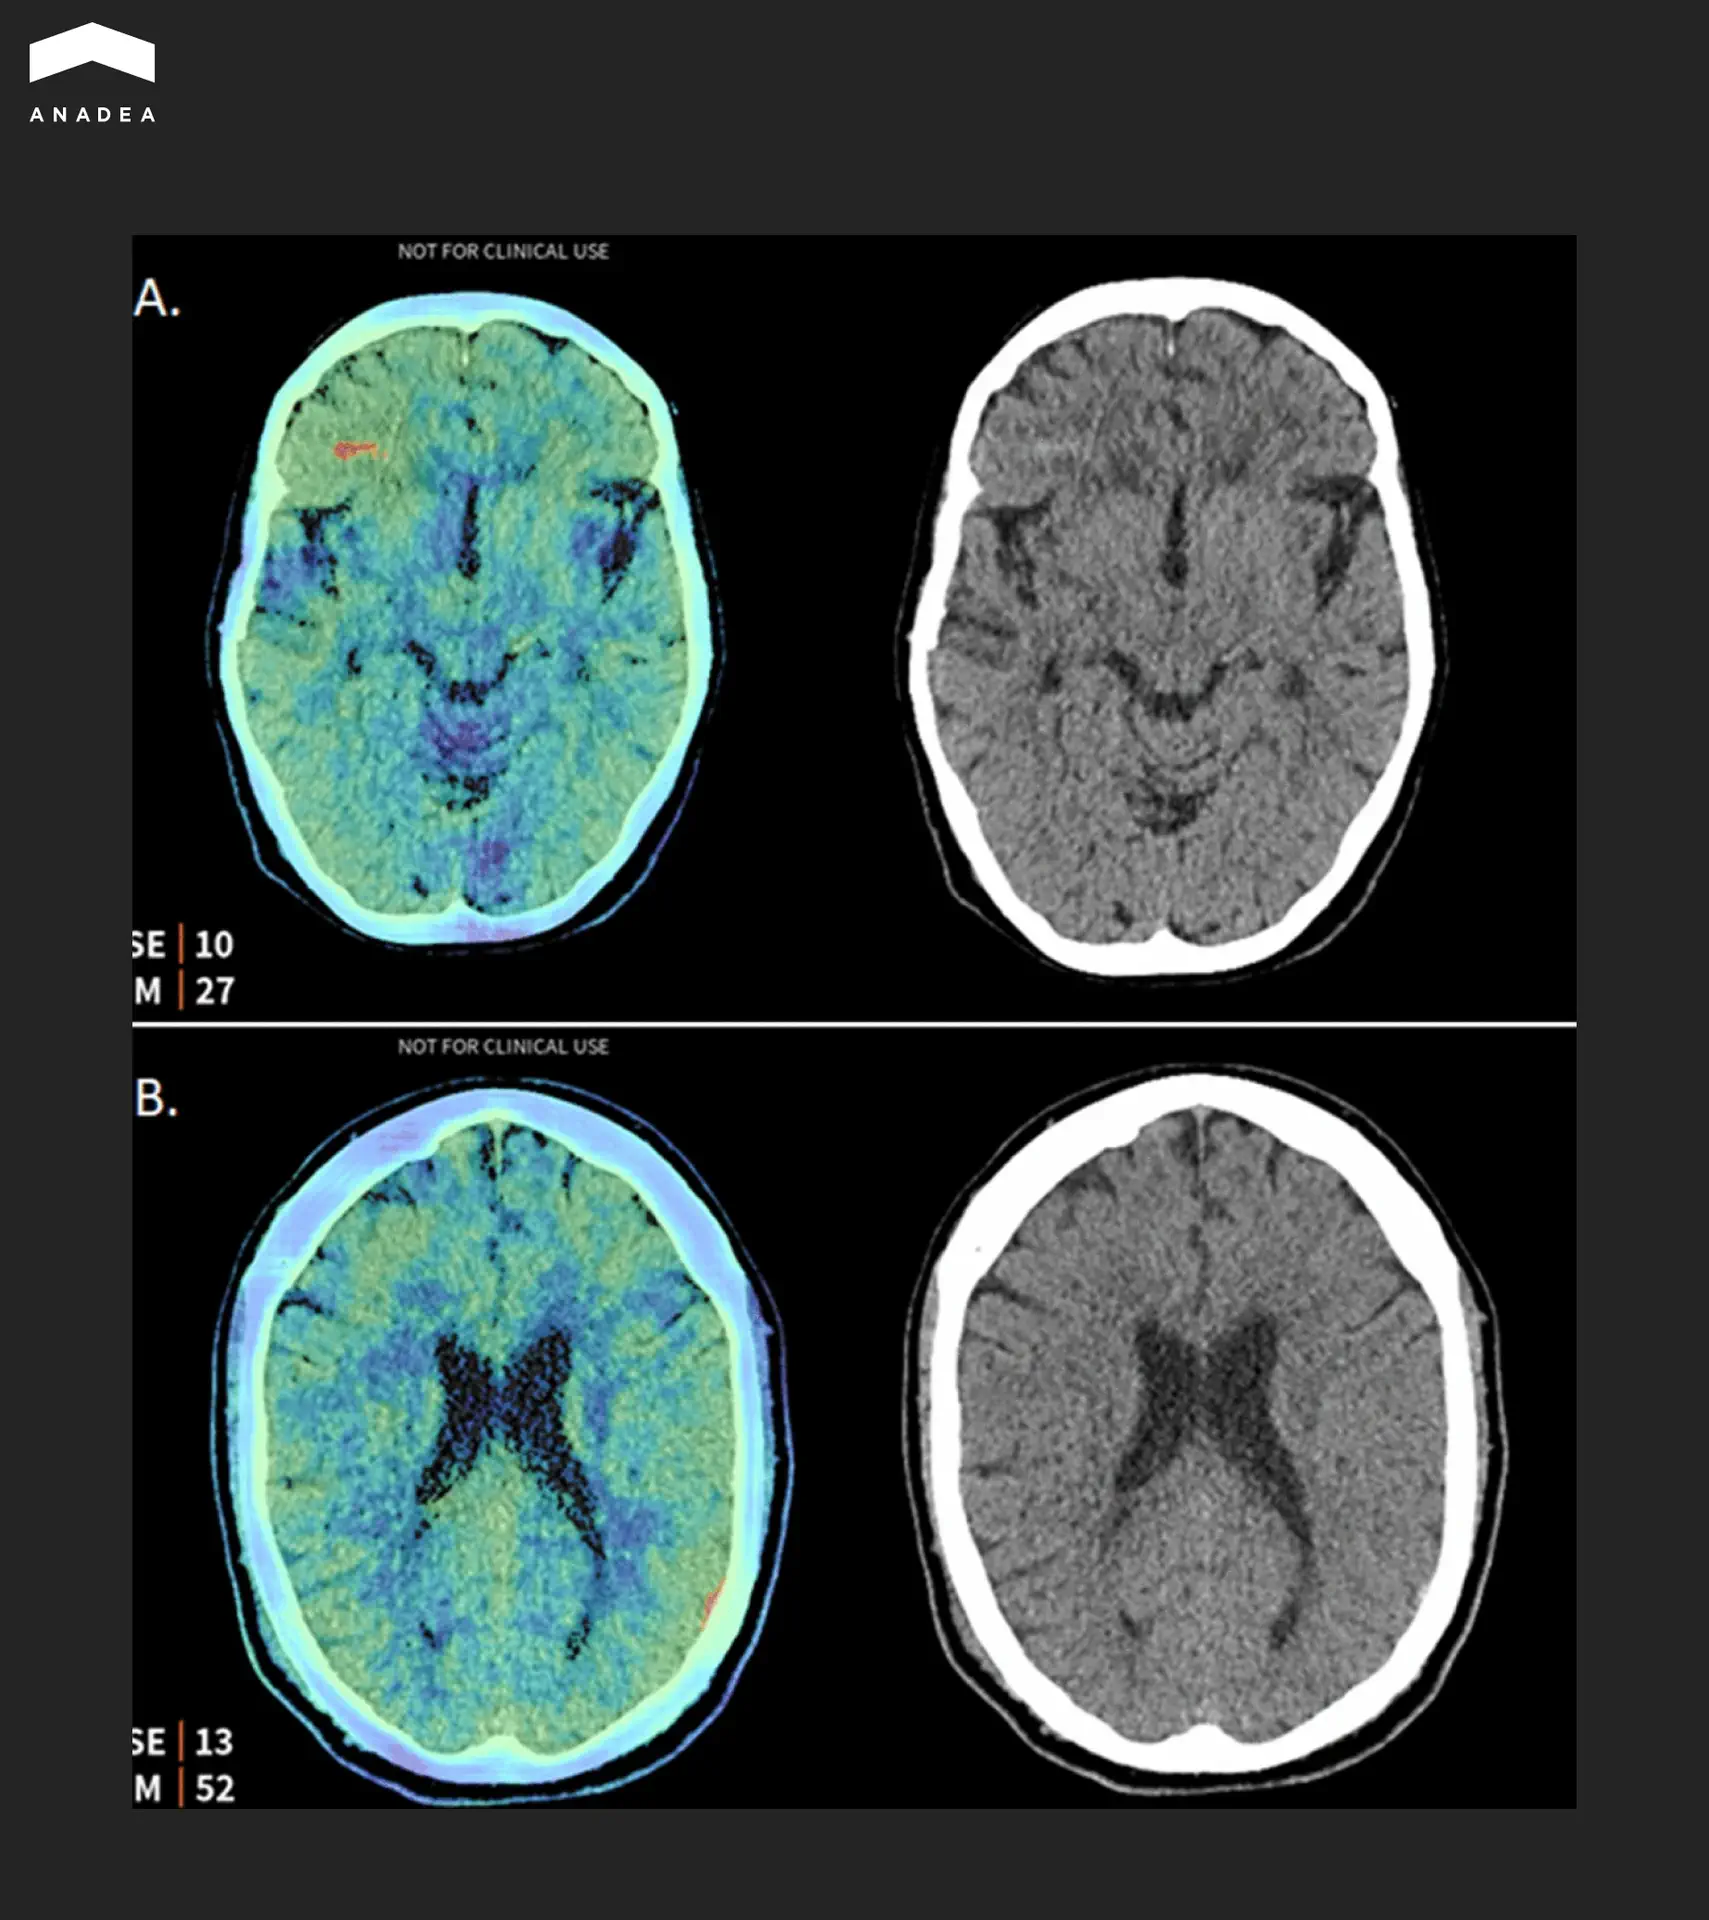

The image below shows an example of such a system in action. The Aidoc algorithm analyzed a brain CT study and detected two hemorrhages that were missed during the initial reading by the radiologist. The left side of each pair shows a saliency map indicating the areas where the algorithm focused its attention. The right side shows the original CT slice.